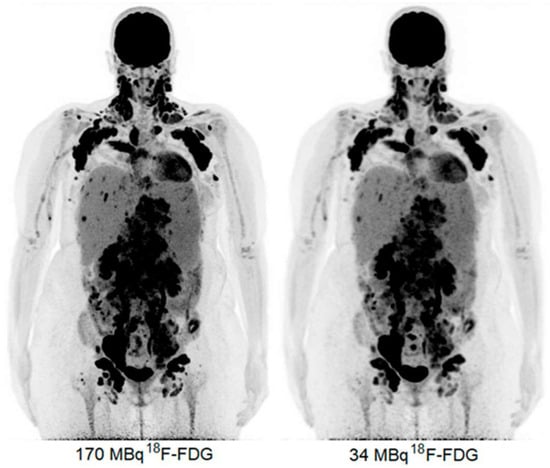

- Sui, X.; Tan, H.; Yu, H.; Xiao, J.; Qi, C.; Cao, Y.; Chen, S.; Zhang, Y.; Hu, P.; Shi, H. Exploration of the total-body PET/CT reconstruction protocol with ultra-low (18)F-FDG activity over a wide range of patient body mass indices. EJNMMI Phys. 2022, 9, 17. [Google Scholar] [CrossRef] [PubMed]